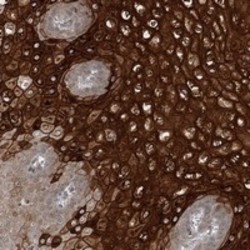

Supportive validation

- Submitted by

- Abnova Corporation (provider)

- Main image

- Experimental details

- Immunohistochemical staining of human esophagus with C10orf62 polyclonal antibody (Cat # PAB23075) shows strong cytoplasmic and membranous positivity in squamous epithelial cells at 1:200-1:500 dilution.

- Validation comment

- Immunohistochemistry (Formalin/PFA-fixed paraffin-embedded sections)